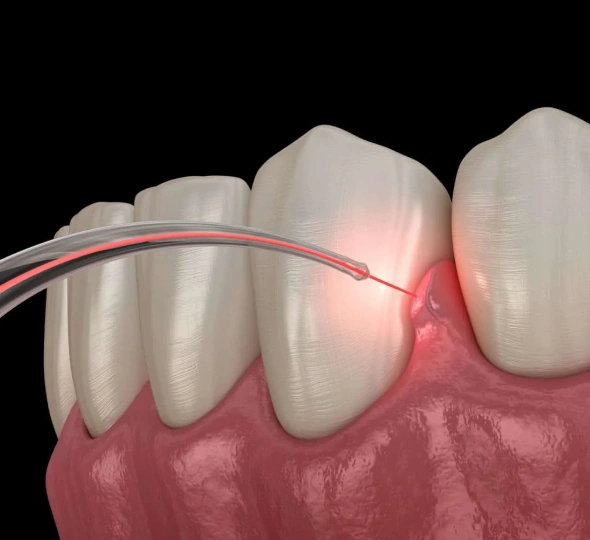

Laser-assisted new attachment procedure (LANAP) is a minimally invasive surgical therapy used to address moderate to severe gum disease. This cutting-edge procedure is the only laser gum disease treatment that has been cleared by the FDA as a true method of periodontal regeneration that enables the reattachment of gum tissues and new bone growth.

LANAP laser dentistry is designed to target the diseased areas of the gum to reduce inflammation and clear away the infected areas. A local anesthetic is applied to the gums and the super-fine, high-powered dental laser is inserted between the infected tooth and gum. A sophisticated tool, the dental laser recognizes and avoids healthy tissue, focusing only on the areas that need healing.